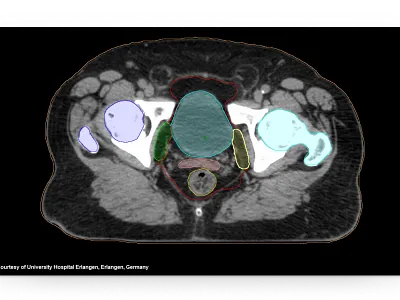

AI-Rad Companion Organs RT

Achieve consistent, high-quality OAR contours using state-of-the-art AI algorithms